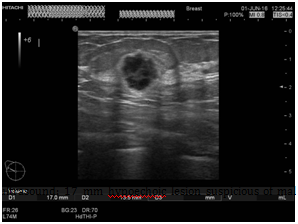

A 43years old white premenopausal female patient admitted though Emergency Department with a recent history of unwell feeling in addition to sudden onset of dizziness, ataxia, vomiting & loss of vision on right eye. Initial clinical assessment revealed loss of coordination, as well as blind right eye and partial unilateral deafness. The patient partner pointed to a smaller pigmented nevus in the anterior chest wall which started to be darker recently. Clinically, there is bilateral indeterminate scattered breast modularity and a small breast lump at the outer upper quadrant of the right breast measures about 30mm. Mammogram and breast US showed bilateral scattered irregular hypo echoic suspicious lesions measures between 5mm & 20mm , graded as M4U4. [BI-RADS: Breast Imaging Reporting and Data System]. A core biopsy was taken from the largest lesion in the right breast (Figure 1) (Figure 2).

Figure 2 Beast ultrasound: 17mm hypoechoic lesion suspicious of malignancy at 10 o’clock position of right breast.